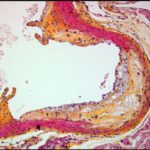

Immagine: una cellula staminale del cancro, prima e dopo il trattamento con composti di semi d’uva. Credit: Patrick Mansell.

Composti presenti nell’uva hanno dimostrato di uccidere le cellule staminali del cancro del colon, sia in una Piastra di Petri che nei topi, secondo un team di ricercatori.

“La combinazione di resveratrolo ed estratto di semi d’uva è molto efficace nell’uccidere le cellule del cancro del colon”, ha detto Vanamala, che è anche un membro di facoltà presso la Penn State Hershey Cancer Institute. “E la cosa importante è che la combinazione di questi composti non è tossica per le cellule sane”.

I ricercatori riferiscono che se assunti separatamente a basse dosi, resveratrolo e estratto di semi d’uva non sono efficaci contro la soppressione delle cellule staminali del cancro, come quando sono somministrati in combinazione.

L’incidenza di tumori è stata soppressa nei topi trattati con i composti di uva del 50 per cento, un tasso simile al tasso del gruppo trattato con sulindac.